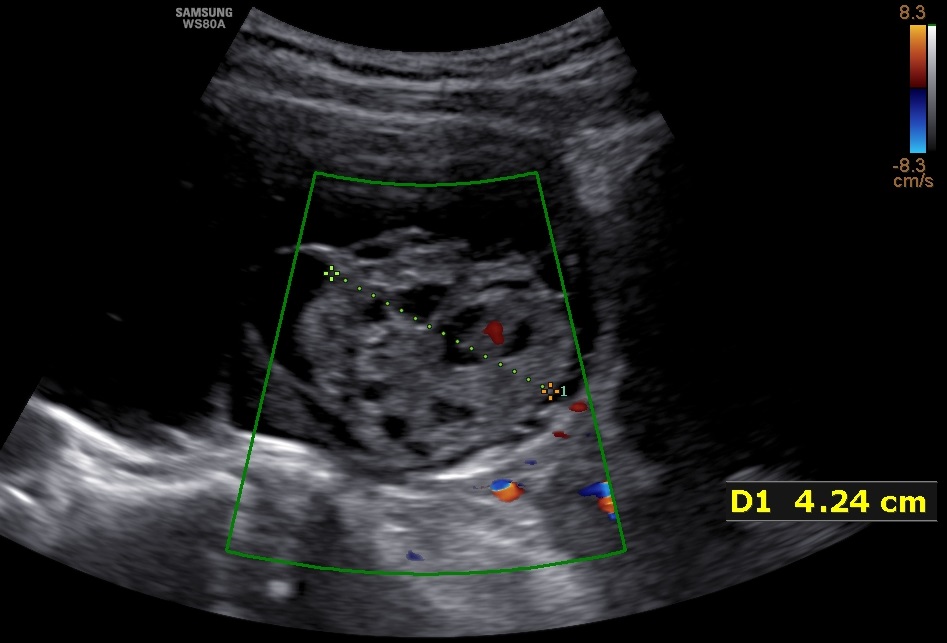

- 31-year old P1 with unilateral, 11.5cm large, multilocular, cystic ovarian tumor with solid components up to 4.2cm cointaining feeding vessels in doppler-sonography. CA-125 was negative. The patient desired further future pregnancies.